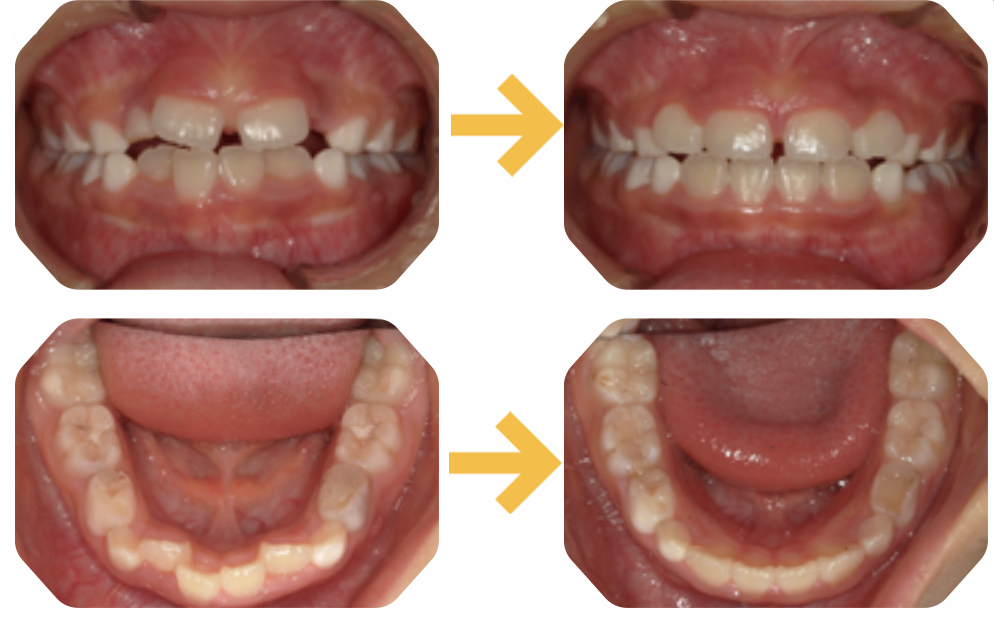

治療後1年の変化

毎日の頑張りの成果があり、ここまで良くなりました。

ハの字になっていた上の前歯もまっすぐになり下の歯のガタつきも改善しています。